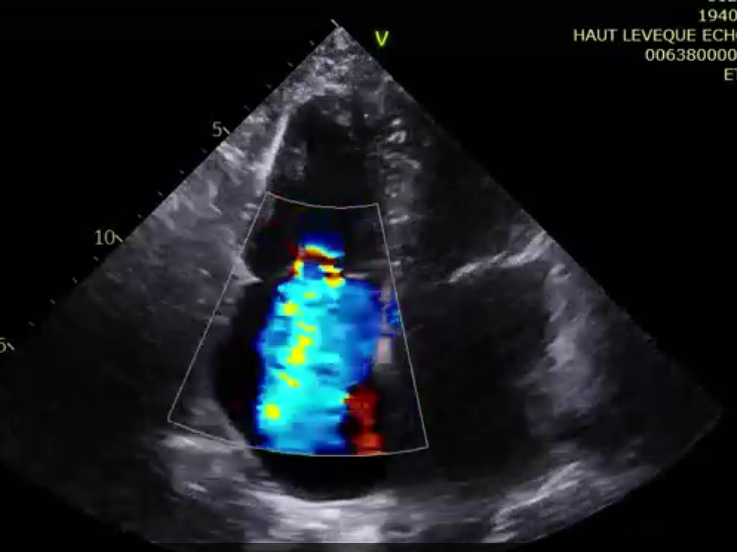

第二名患者是一位79歲的女性,術(shù)前TTE診斷TR等級4+,既往有高血壓、腎功能不全、肺動(dòng)脈高壓的病史。術(shù)者在擁有第一臺手術(shù)的經(jīng)驗(yàn)后,在TEE和DSA的引導(dǎo)下非常順利地完成瓣膜的釋放,術(shù)后瓣膜形態(tài)穩(wěn)定,TEE提示即刻反流0+?;颊咝g(shù)后七天TTE復(fù)查提示無明顯三尖瓣反流,瓣膜整體形態(tài)非常穩(wěn)定。

術(shù)前超聲提示大量三尖瓣反流